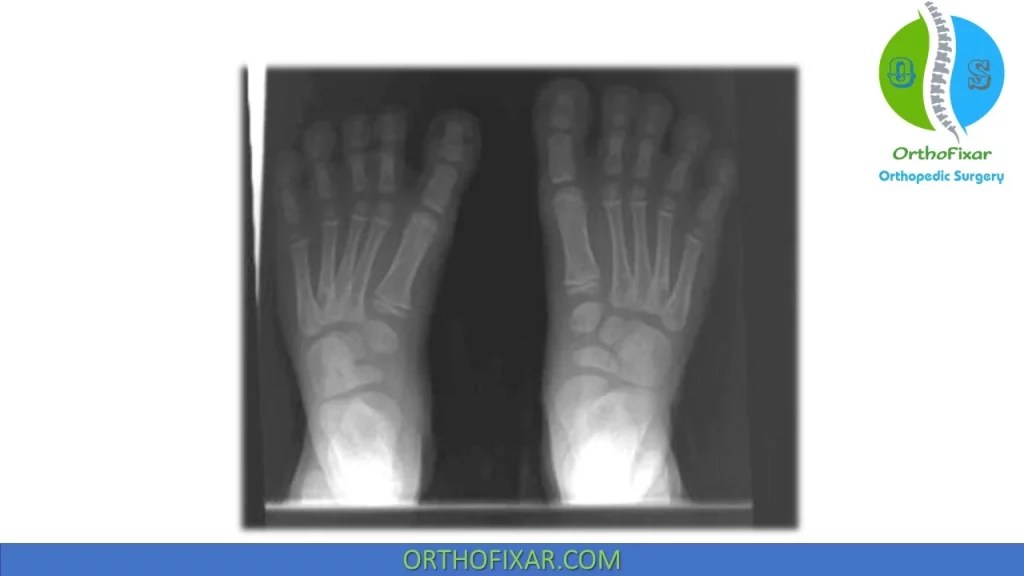

Metatarsus Adductus Xray What Is Metatarsus Primus Adductus If your child has metatarsus adductus, you may notice that his or her foot has a curved shape. Metatarsus primus varus is a foot deformity that affects the angle of the bones of the big toe. Metatarsus adductus, also known as metatarsus varus, is a common foot deformity that causes the front half of the foot, or forefoot, to turn. What Is Metatarsus Primus Adductus.

Metatarsus adductus Image What Is Metatarsus Primus Adductus What are the signs and symptoms of metatarsus adductus? If your child has metatarsus adductus, you may notice that his or her foot has a curved shape. This causes a visible deformity, and both feet are often affected. It's also associated with a bunion, which is a bump on the side of the big toe. Metatarsus adductus refers to a. What Is Metatarsus Primus Adductus.

Metatarsus Adductus Xray What Is Metatarsus Primus Adductus Metatarsus adductus occurs when the forefoot of an adult turns inward, causing pain, discomfort, and biomechanical issues. Metatarsus adductus refers to a condition where the metatarsal bones are turned toward the middle of the body. If your child has metatarsus adductus, you may notice that his or her foot has a curved shape. It is an adduction deformity or medial. What Is Metatarsus Primus Adductus.

Metatarsus Adductus Xray What Is Metatarsus Primus Adductus Metatarsus primus varus is a foot deformity that affects the angle of the bones of the big toe. Metatarsus adductus refers to a condition where the metatarsal bones are turned toward the middle of the body. What are the signs and symptoms of metatarsus adductus? It is an adduction deformity or medial deviation of the forefoot at the. This causes. What Is Metatarsus Primus Adductus.